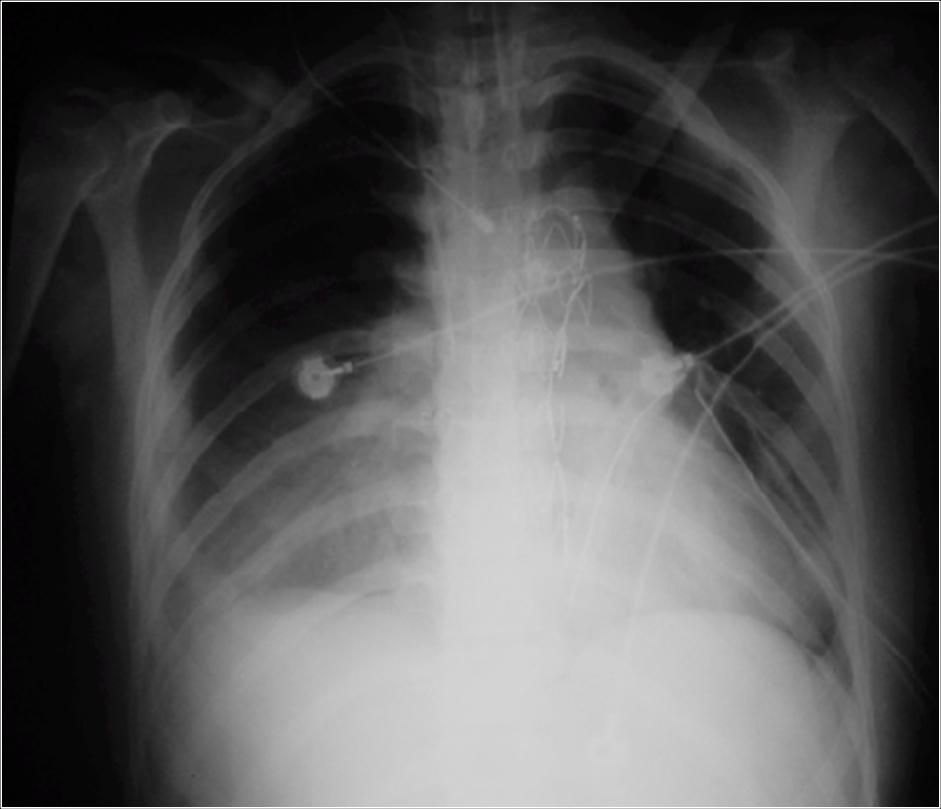

After Procedure

The outcome was excellent and the patient is in good shape rightnow with a normal lifestyle.